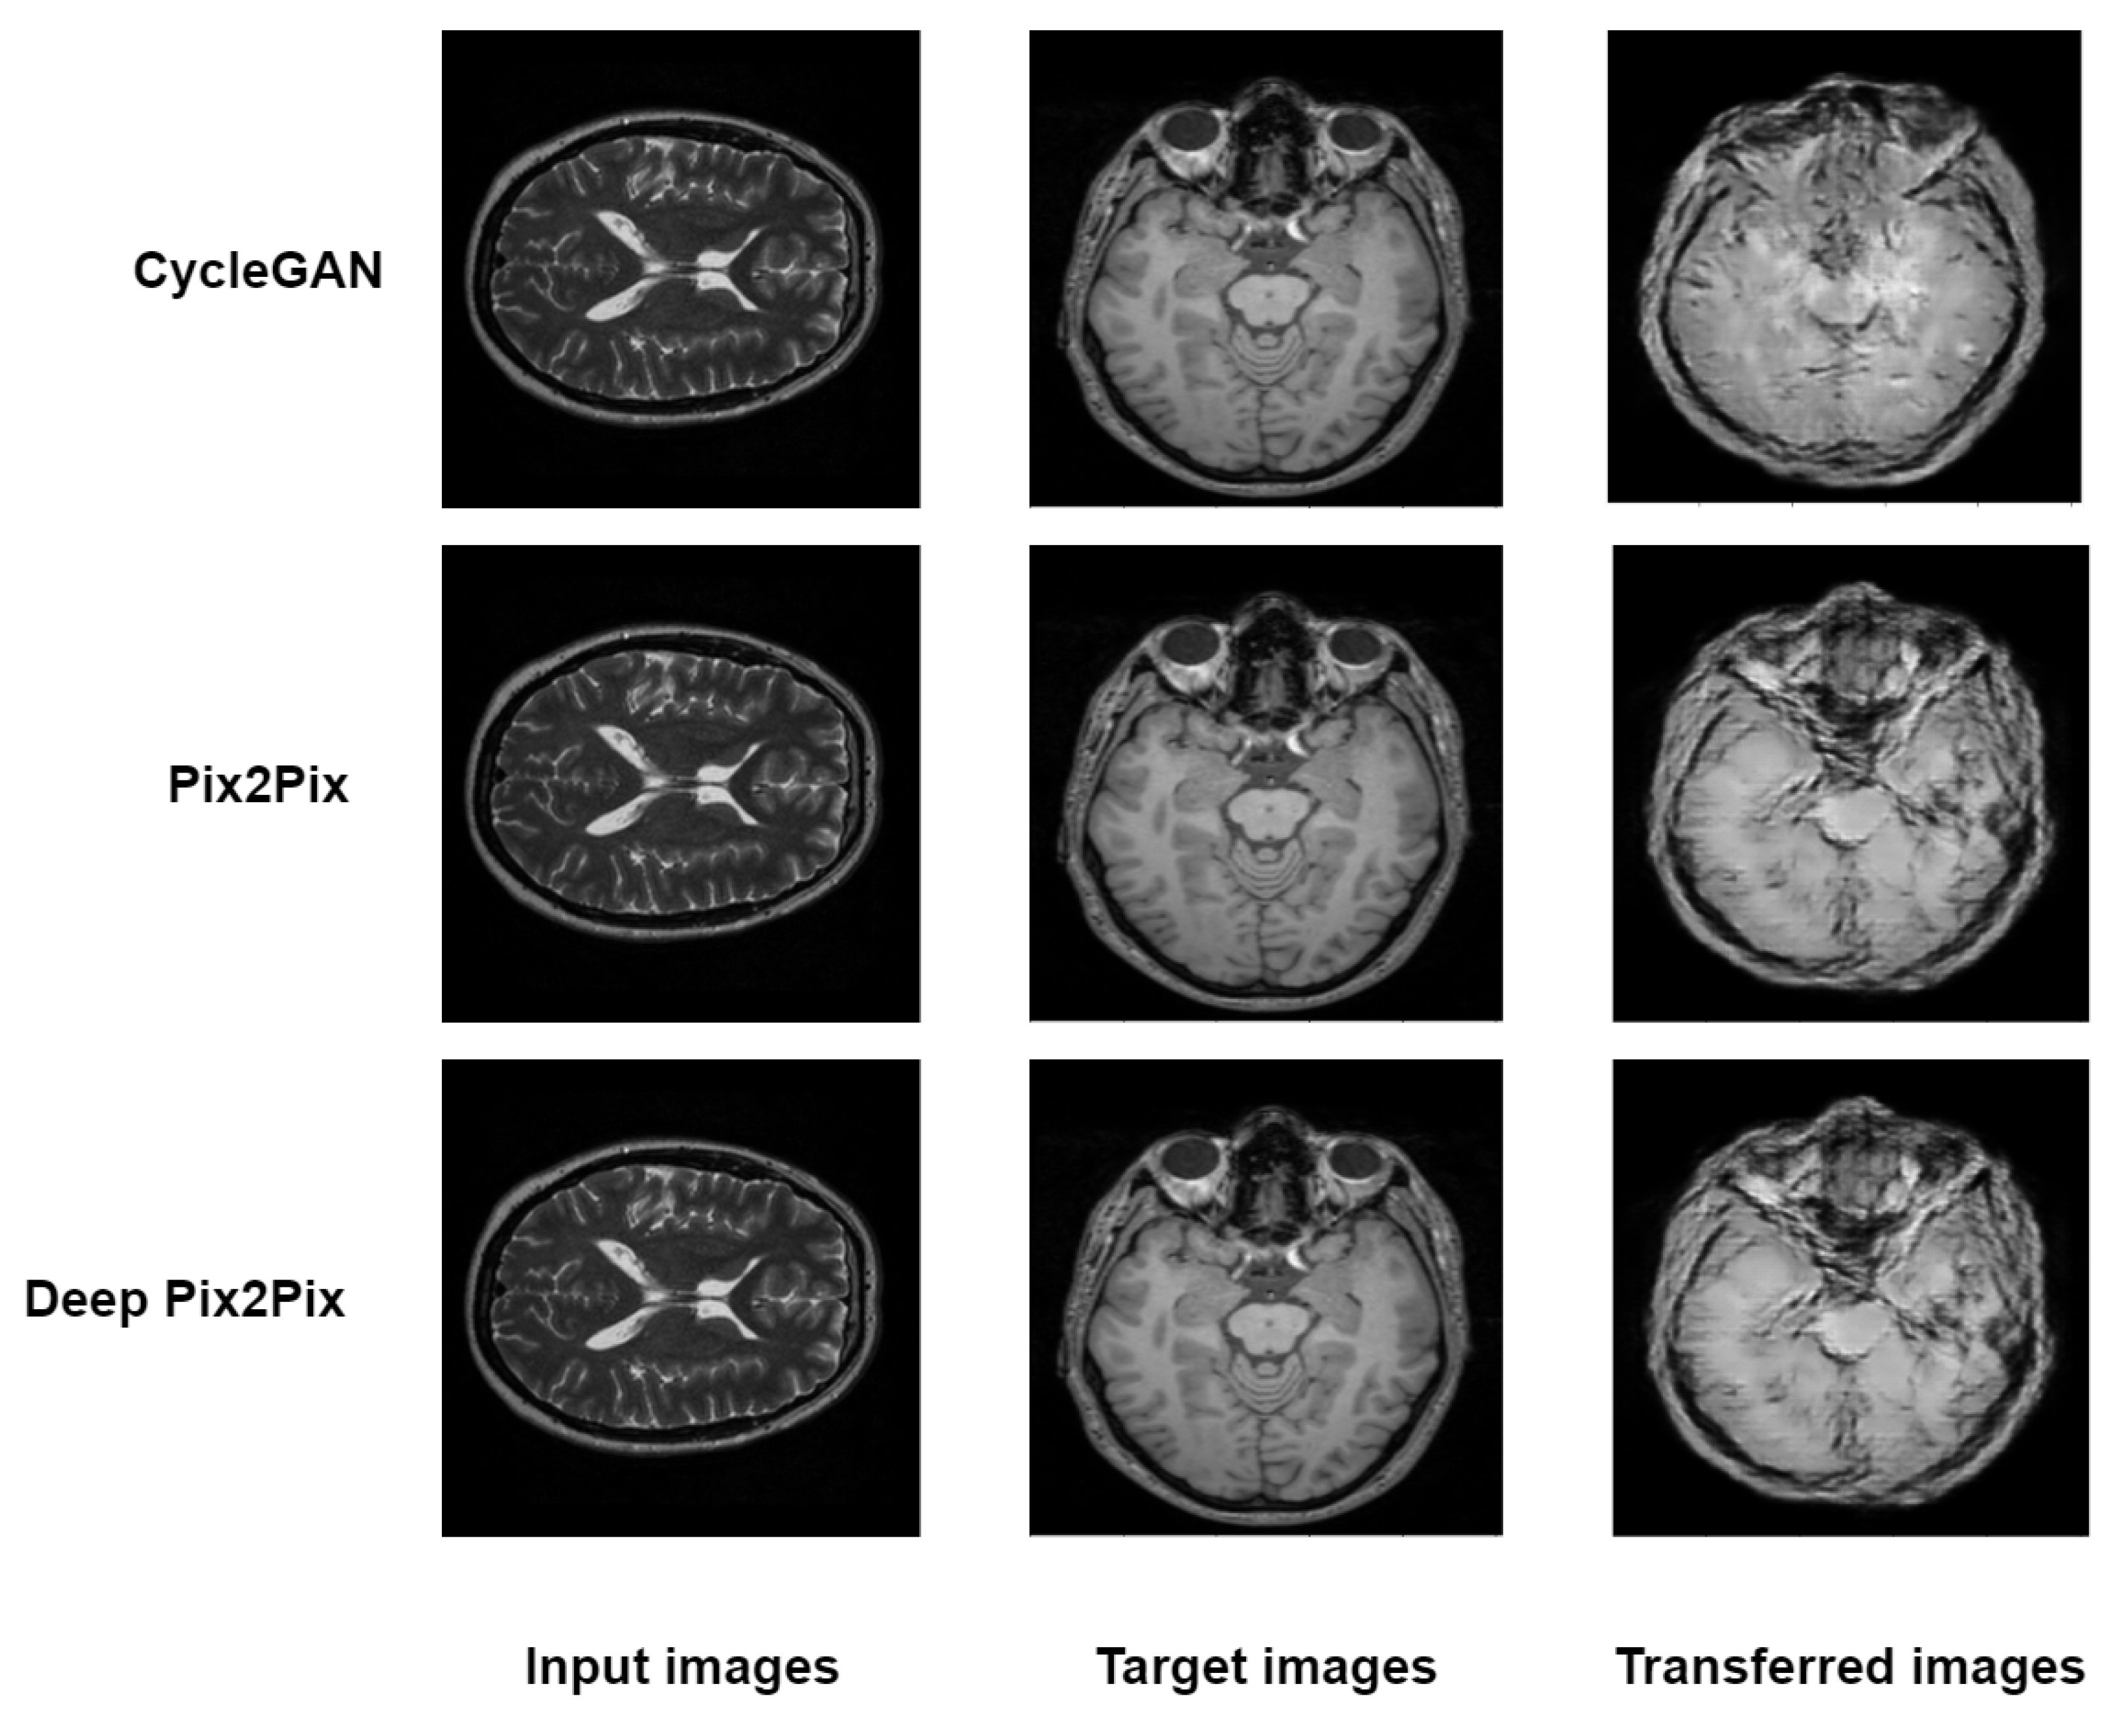

The three models, including cyclegan, pix2pix and proposed deep pix2pix, try to generate synthetic images from one view to another view for qualitative analysis. As shown in Figure 3, the proposed deep pix2pix model shows the most accurate result compared to the rest of the models used in the experiment, while the cyclegan model performs the worst qualitative analysis.

Figure 3.

Testing images of CycleGan, Pix2Pix and Deep Pix2Pix.